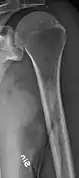

Humerus with multiple myeloma lesions

Same humerus before, with just subtle lesions

The diagnostic examination of a person with suspected multiple myeloma typically includes a skeletal survey. This is a series of X-rays of the skull, axial skeleton, and proximal long bones. Myeloma activity sometimes appears as "lytic lesions" (with local disappearance of normal bone due to resorption). And on the skull X-ray as "punched-out lesions" (pepper-pot skull). Lesions may also be sclerotic, which is seen as radiodense.[47] Overall, the radiodensity of myeloma is between −30 and 120 Hounsfield units (HU).[48] Magnetic resonance imaging is more sensitive than simple X-rays in the detection of lytic lesions, and may supersede a skeletal survey, especially when vertebral disease is suspected. Occasionally, a CT scan is performed to measure the size of soft-tissue plasmacytomas. Bone scans are typically not of any additional value in the workup of people with myeloma (no new bone formation; lytic lesions not well visualized on bone scan).